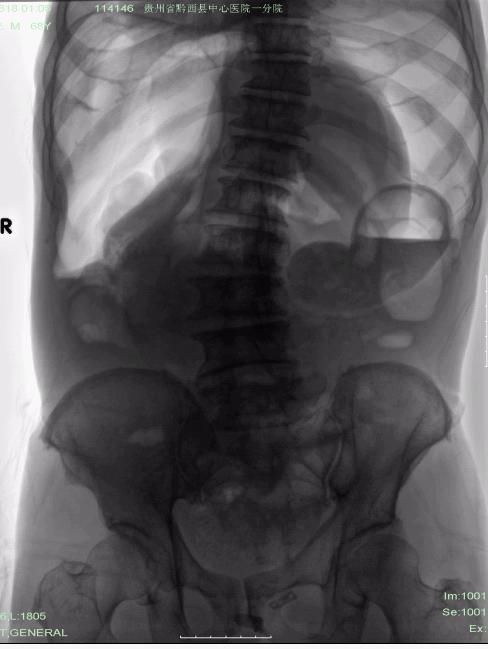

男,68岁,腹痛20多天。

气腹成这样能忍受,不是痛阙高就是反射弧有问题,([悄悄话]要不就是cp?)

气腹?..........我还以为肠梗阻呢?张力那么高!!!不要搞错了浪费病人的病情就行~~~~~

气腹,见宽大气液平, 太恐怖啦吧。

典型的大量气腹----消化道穿孔。

大量气腹。考虑胃肠穿孔可能。

大量气腹;多为腹部空腔脏器穿孔所致。